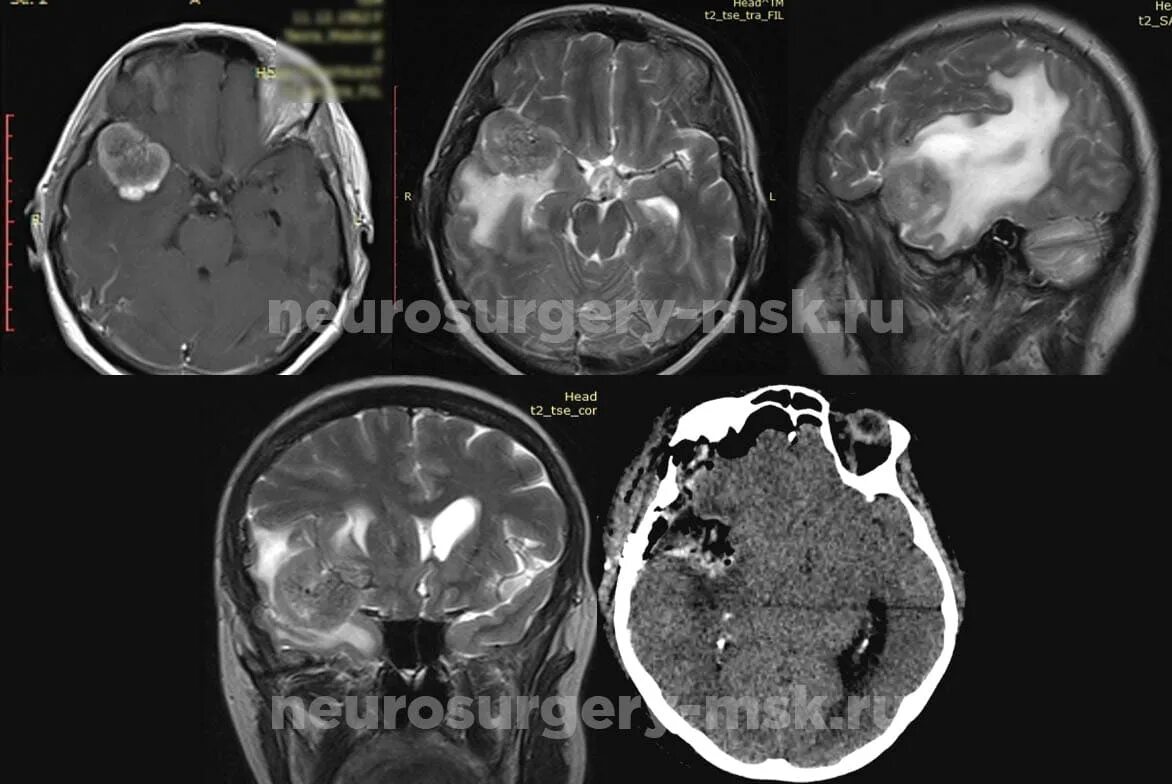

Метастазы в головном мозге мкб